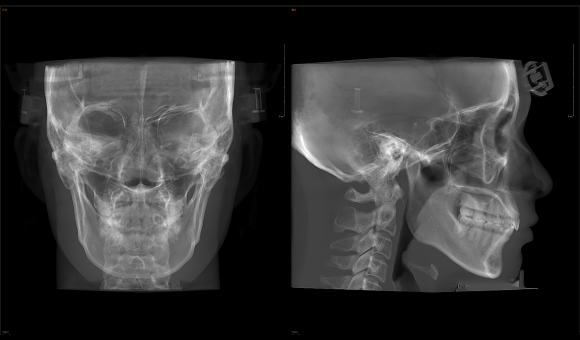

只需一次单圈扫描即可获得CT、3D全景和3D正/侧位影像,并能同时生成3D TMJ视图

提高诊疗效率,避免过度检查,减少患者所受的辐射

• 3D 正侧位

3D 正侧位